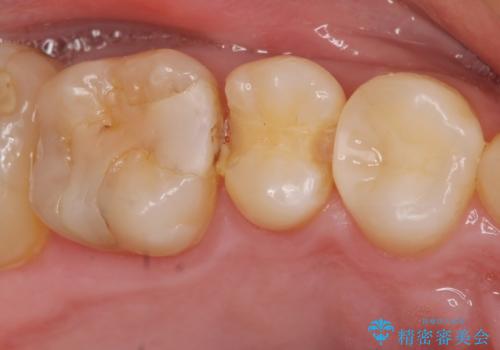

窩洞形態により選択するインレーの素材

- 定期検診を希望され来院、虫歯が発見されたため治療へと移行しました。

虫歯の大きさや残存歯質・窩洞形態によりゴールドやセラミックといった材質を選択することでより歯を削る量を少なくすると同時に強度も確保、長期的な予後を期待できるような治療を実践していきます。

セラミック・ゴールド共に化学的な変化が少なくインレー素材として理想的ですが、色調や強度・加工のしやすさ・最低限必要な厚み等の条件が異なります。

今回の治療では、虫歯を除去したのちより修復に適した素材を選択することで歯を削る量を可及的に少なくすることと、長期的な予後を期待できるような状態にすることができました。